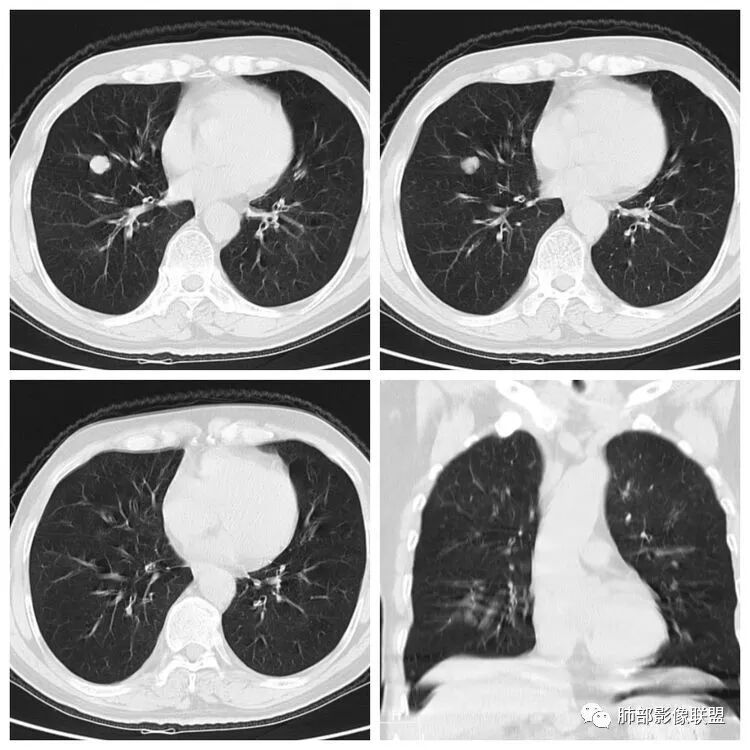

老年女性,吸烟史,右肺中叶外侧段结节,局部突起,浅分叶,右肺中叶外侧段支气管进入截断,病理不会看,无增强,常规考虑1,鳞癌。2,错构瘤。

右肺中叶实性结节,边缘光整,部分平直、部分膨隆,浅分叶,与支气管关系不明确,考虑良性结节,错构瘤?

右肺中叶实性结节,边缘较光整,以膨隆为主,浅分叶,部分与支气管相连,挂果征?但一般是挂在分支气管末端,首先考虑良性病变,错构?有吸烟病史,恶性也不能完全除外。

患者老年男性,体检发现右肺占位1天。有“高血压、脑出血、胃息肉术后、腰椎压缩性骨折”病史。胸部CT:右肺中叶外侧段紧贴叶间裂不规则实性结节,边界清楚、膨隆,见血管穿行,支气管远端堵塞。结合长期大量吸烟史。考虑恶性病变,病理不会,小细胞癌可能。鉴别鳞癌、错构瘤或平滑肌瘤。

右肺结节,形态似葫芦样,边缘平直彭隆,分叶及坏死不明显,近段可见增粗的血管及清晰的磨玻璃影,部分支气管似穿行,考虑炎性结节(错构瘤,腺瘤PSP),鉴别小细胞癌

右肺中叶结节,位于叶间胸膜下,无明显胸膜牵拉,说明收缩力不强,结节整体边缘膨隆、分叶,局部局限性突出,像个小尾巴,密度不均匀,可见支气管进入,远端显示欠清晰,病理图不会看,首先考虑小细胞肺癌,鉴别错构瘤,转移瘤

右肺上叶实性结节,边缘清楚、膨隆,浅分叶,血管穿行,重建示支气管进入后阻塞 ,总体倾向恶性。

LCNEC最常见的影像特征包括:(1)肿块发生部位:周围型肺癌为主,少数发生于肺中央。(2)肿块大小及形态。因肿瘤细胞生长迅速常形成较大肿块,因此其体积一般较大,直径常在3~10cm范围内,病灶常为不规则形软组织肿块。(3)肿块边界。多数学者报道大多数肿块边界清晰光整,边缘可呈分叶状,收缩能力不强,毛刺征及“胸膜凹陷征”少见,病灶附近常干净。认为与该病对周围组织浸润较轻及较少产生纤维瘢痕组织牵拉有关联。(4)肿块密度、强化特点及代谢情况。据文献报道,该类肿瘤因体积较大CT上常见软组织肿块,部分密度较均匀,病灶较大者可以观察到囊变坏死区,增强后呈轻或中度不均匀强化(可见强化者占75.7%),认为其强化特点与其内部肉眼可见坏死灶和肿瘤较大直径有关。(5)伴随症状及远处转移。该病恶性程度高,侵袭性强,常侵犯邻近结构,如胸膜、心包、邻近骨质或纵隔内组织等,易出现纵隔淋巴结转移,部分发生肺内及远处转移,少数早期可出现广泛远处转移。

一个“骨肉匀称”的结节,有可能是天使(错构瘤、硬化性肺细胞瘤PSP),也有可能是恶魔(转移瘤、类癌、大细胞神经内分泌癌等)

1.硬化性肺细胞瘤:类圆形很少分叶,没有血管支气管进入,密度均匀,大多显著强化!

2.错构瘤:常有浅分叶,周围也干净,脂质密度区及爆米花样钙化都具有较为特征性意义。病灶不会显著强化。

3.转移瘤:有原发肿瘤病史,孤立灶相对少见。多类圆形,支气管进入常常是反指征!

4.小细胞癌:可以是干净光滑的小结节,但常可观察到显著增大的肺门纵隔淋巴结!

5.大细胞癌:结节往往较大,生长较快,注意肺门纵隔增大的淋巴结不似小细胞癌那么夸张!

本例未行增强扫描!精准影像,技术先行,有完整的图像及后处理,仔细观察病灶内部的成份(有无钙化、空洞、坏死)及强化情况,观察病灶与支气管、血管的关系,再结合患者病史,才是鉴别良性跟恶性的病灶的制胜砝码,至于病理类型就可以交给病理科。